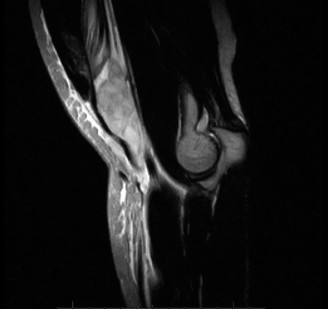

Imaging should include x-rays, which may demonstrate posterior glenoid bone loss or an impaction fracture on the anterior-superior humeral head (Fig. 2–38). CT images with 3D reconstructions can be very useful when assessing the extent of glenoid bone loss and evaluating glenoid and humeral version. Normal glenoid version is from −2 to −8 degrees of retroversion, and this may be increased in posterior instability. MRI can also be useful when assessing the posterior labrum (Fig. 2–39).

Figure 2–39 MRI showing a posterior labrum tear.